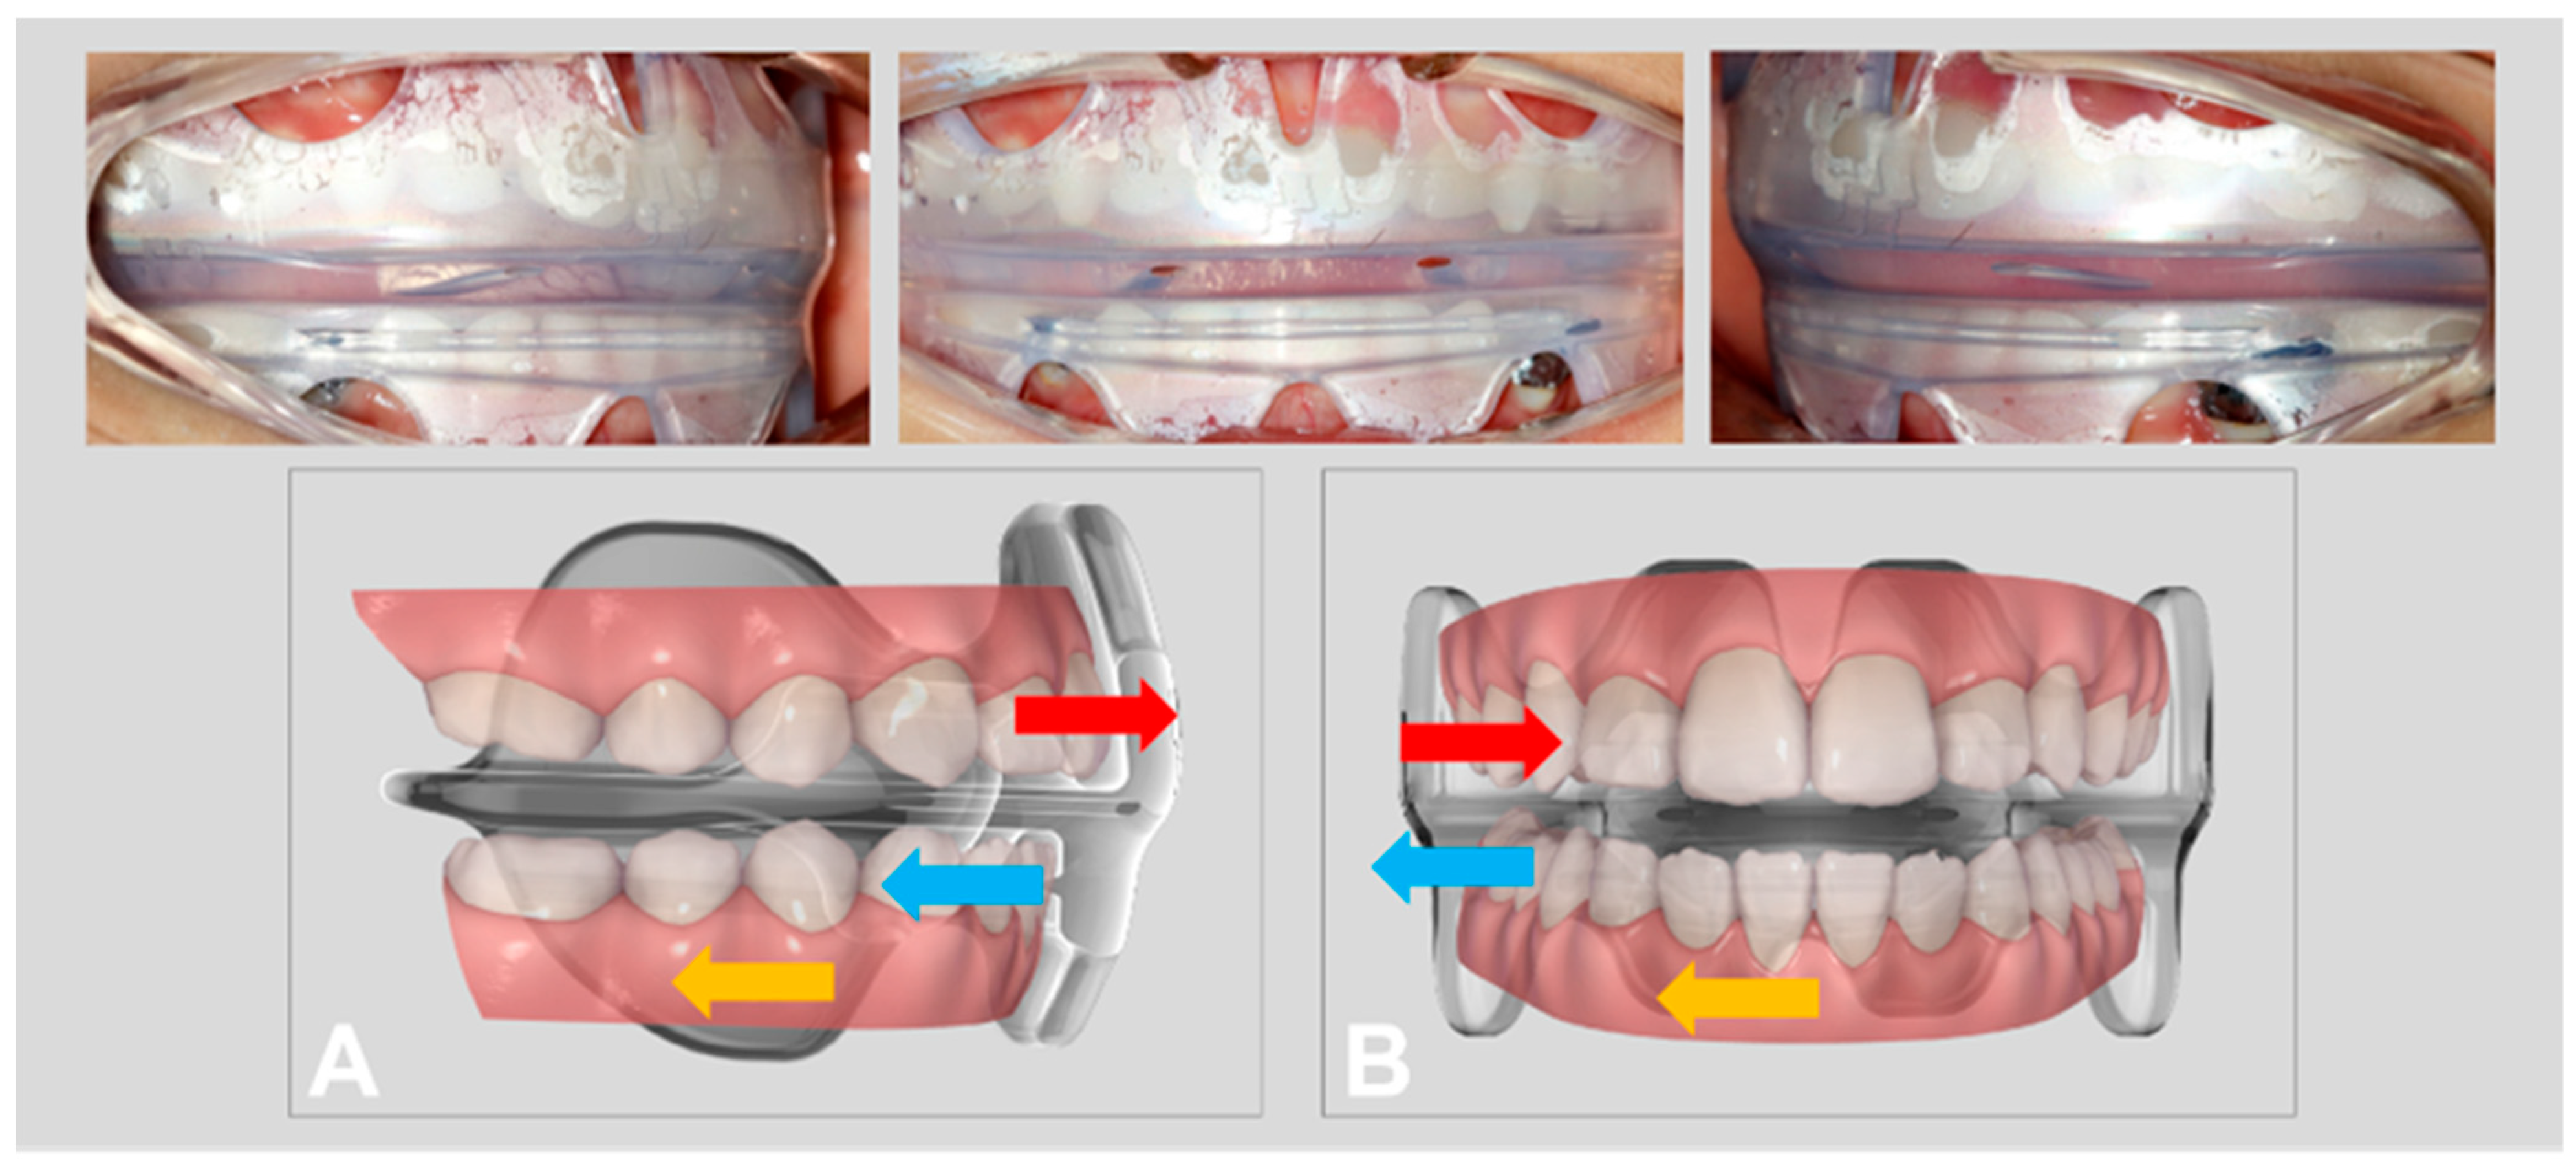

2.5. Treatment Sequence

3. Results